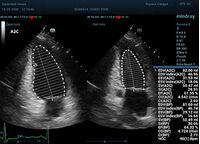

С появлением В режима реализовалась возможность визуализации всех сегментов миокарда из парастернальных и апикальных сечений. Метод Teicholtz в широкой практике сменился методом дисков. Метод дисков, или метод Simpson, позволяет разбить левый желудочек на 20 дисков, с расчетом объема каждого из них. Используя 2 перпендикулярных сечения, апикальные двух и четырех камерное, мы приближаемся к значению реального объема левого желудочка. Исследователь обводит интерфейс эндокард – кровь в фазу диастолы и фазу систолы. Линия простирается от кольца митрального клапана и до кольца митрального клапана, четко разграничивая объем желудочка от предсердия. Для достоверного изменения необходимо использовать ЭКГ канал.

Обводить вручную эти линии занимало много времени, однако результат того стоил. Следующим шагом стало появление Spline технологии, позволяющее расставлять точки и автоматически их соединять. Такой способ планиметрии контура эндокарда значительно сократил время измерения.

Что могут предложить современные приборы? Приборы нашего времени являются мощными вычислительными машинами, способными обрабатывать полученную информацию даже без помощи человека. Система автоматического вычисления фракции выброса – AUTO EF на

приборах серии Resona компании Mindray сделает все за вас. За пару секунд прибор сам отыщет нужную фазу сердечного цикла и произведёт измерение и расчеты, а также покажет график изменения объема в сердечном цикле. От Вас требуется только получить качественное 4С и 2С сечение. Впрочем, прибор всегда оставляет возможность коррекции, если доктор имеет свое мнение на расположение точек планиметрии или момента измерения по ЭКГ каналу.